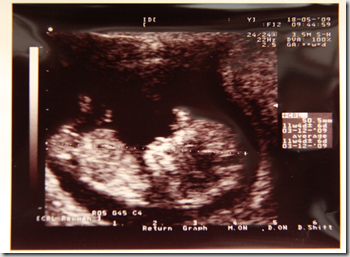

Now we are in week 17, Mojo has grown and is now a full 98.6mm, the head with the eye sockets and nose and chin are more apparent. What is also visible but not apparent here, is Mojo’s fully formed bones which are all in the right place. So all is well, for me it was a sense of relief not that I was worried but, it was just comforting to see Mojo growing well and strong too. Mojo was rolling and turning around through out the visit.

As the gynae was talking to us, Mojo jumped to the other side of the womb. Here you can see the spine more clearly. So now, for the moment we have all been waiting for (at least for the two of us).

Is Mojo a He or a She? With all the movement and jumping that was going on Mojo managed to give us a glimpse of her bum and there was no birdy there so ladies and gentlemen, we are having a GIRL! For now it is 80% certain as per the gynae but in any case, for now we will go with the premise that Mojo is a her!